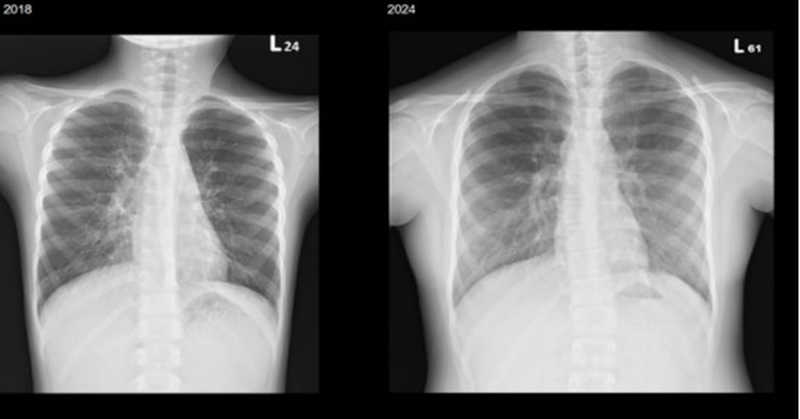

▲林小妹於2018年、2025年所攝胸部X光片,楊佳鳳主任表示,成像愈黑,代表肺功能較好,可見她歷經7年專業照護,肺功能維持穩定。(圖/北榮提供)